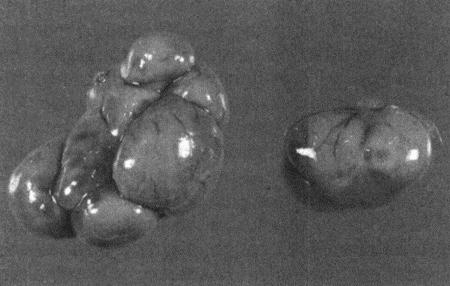

ГЛАВА 3

Бесплодие самок

П. Райт, Д. Уоттс (Patric J. Wright and John R. Watts)

Нарушения, характеризующиеся отсутствием эструса

Анэстрия может проявиться следующим образом: либо у самки в соответствующем возрасте не началась циклическая активность, либо увеличена продолжительность интер-про-эструса (т. е. более 12 месяцев для сук и более 20 дней для кошек), либо прекратилась циклическая активность. Патология обусловливается отсутствием явных признаков проэструса и эструса или структурными либо функциональными нарушениями в системе гипоталамус-гипофиз-яичники.